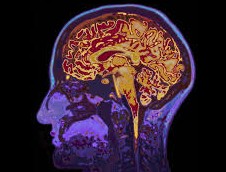

• Une leucoencéphalopathie

Une leucoencéphalopathie, ou leucopathie, désigne l’altération de la substance blanche cérébrale. Chez l’adulte, les leucopathies chroniques sont majoritairement secondaires à des maladies acquises à...